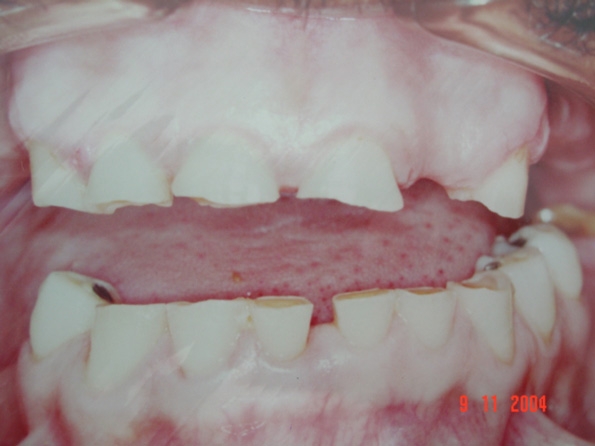

Dores de cabeça e mandibulares são os principais sintomas desse distúrbio que pode se manifestar durante o dia ou noite, geralmente, durante o sono. No entanto, Dr. Goldmann alerta que também pode acarretar outros tipos de problemas. “Desgaste dental, os dentes podem ficar soltos, destruição e sangramento do tecido da gengiva”.

O bruxismo pode ser pertinente em todas as faixas etárias e em ambos os sexos. O tratamento mais utilizado é o uso de uma placa estabilizadora de resina acrílica que protege os dentes, alivia o sistema mastigatório durante as crises de ranger os dentes, além de reduzir a atividade elétrica muscular causadora da tensão dos músculos mastigatório.